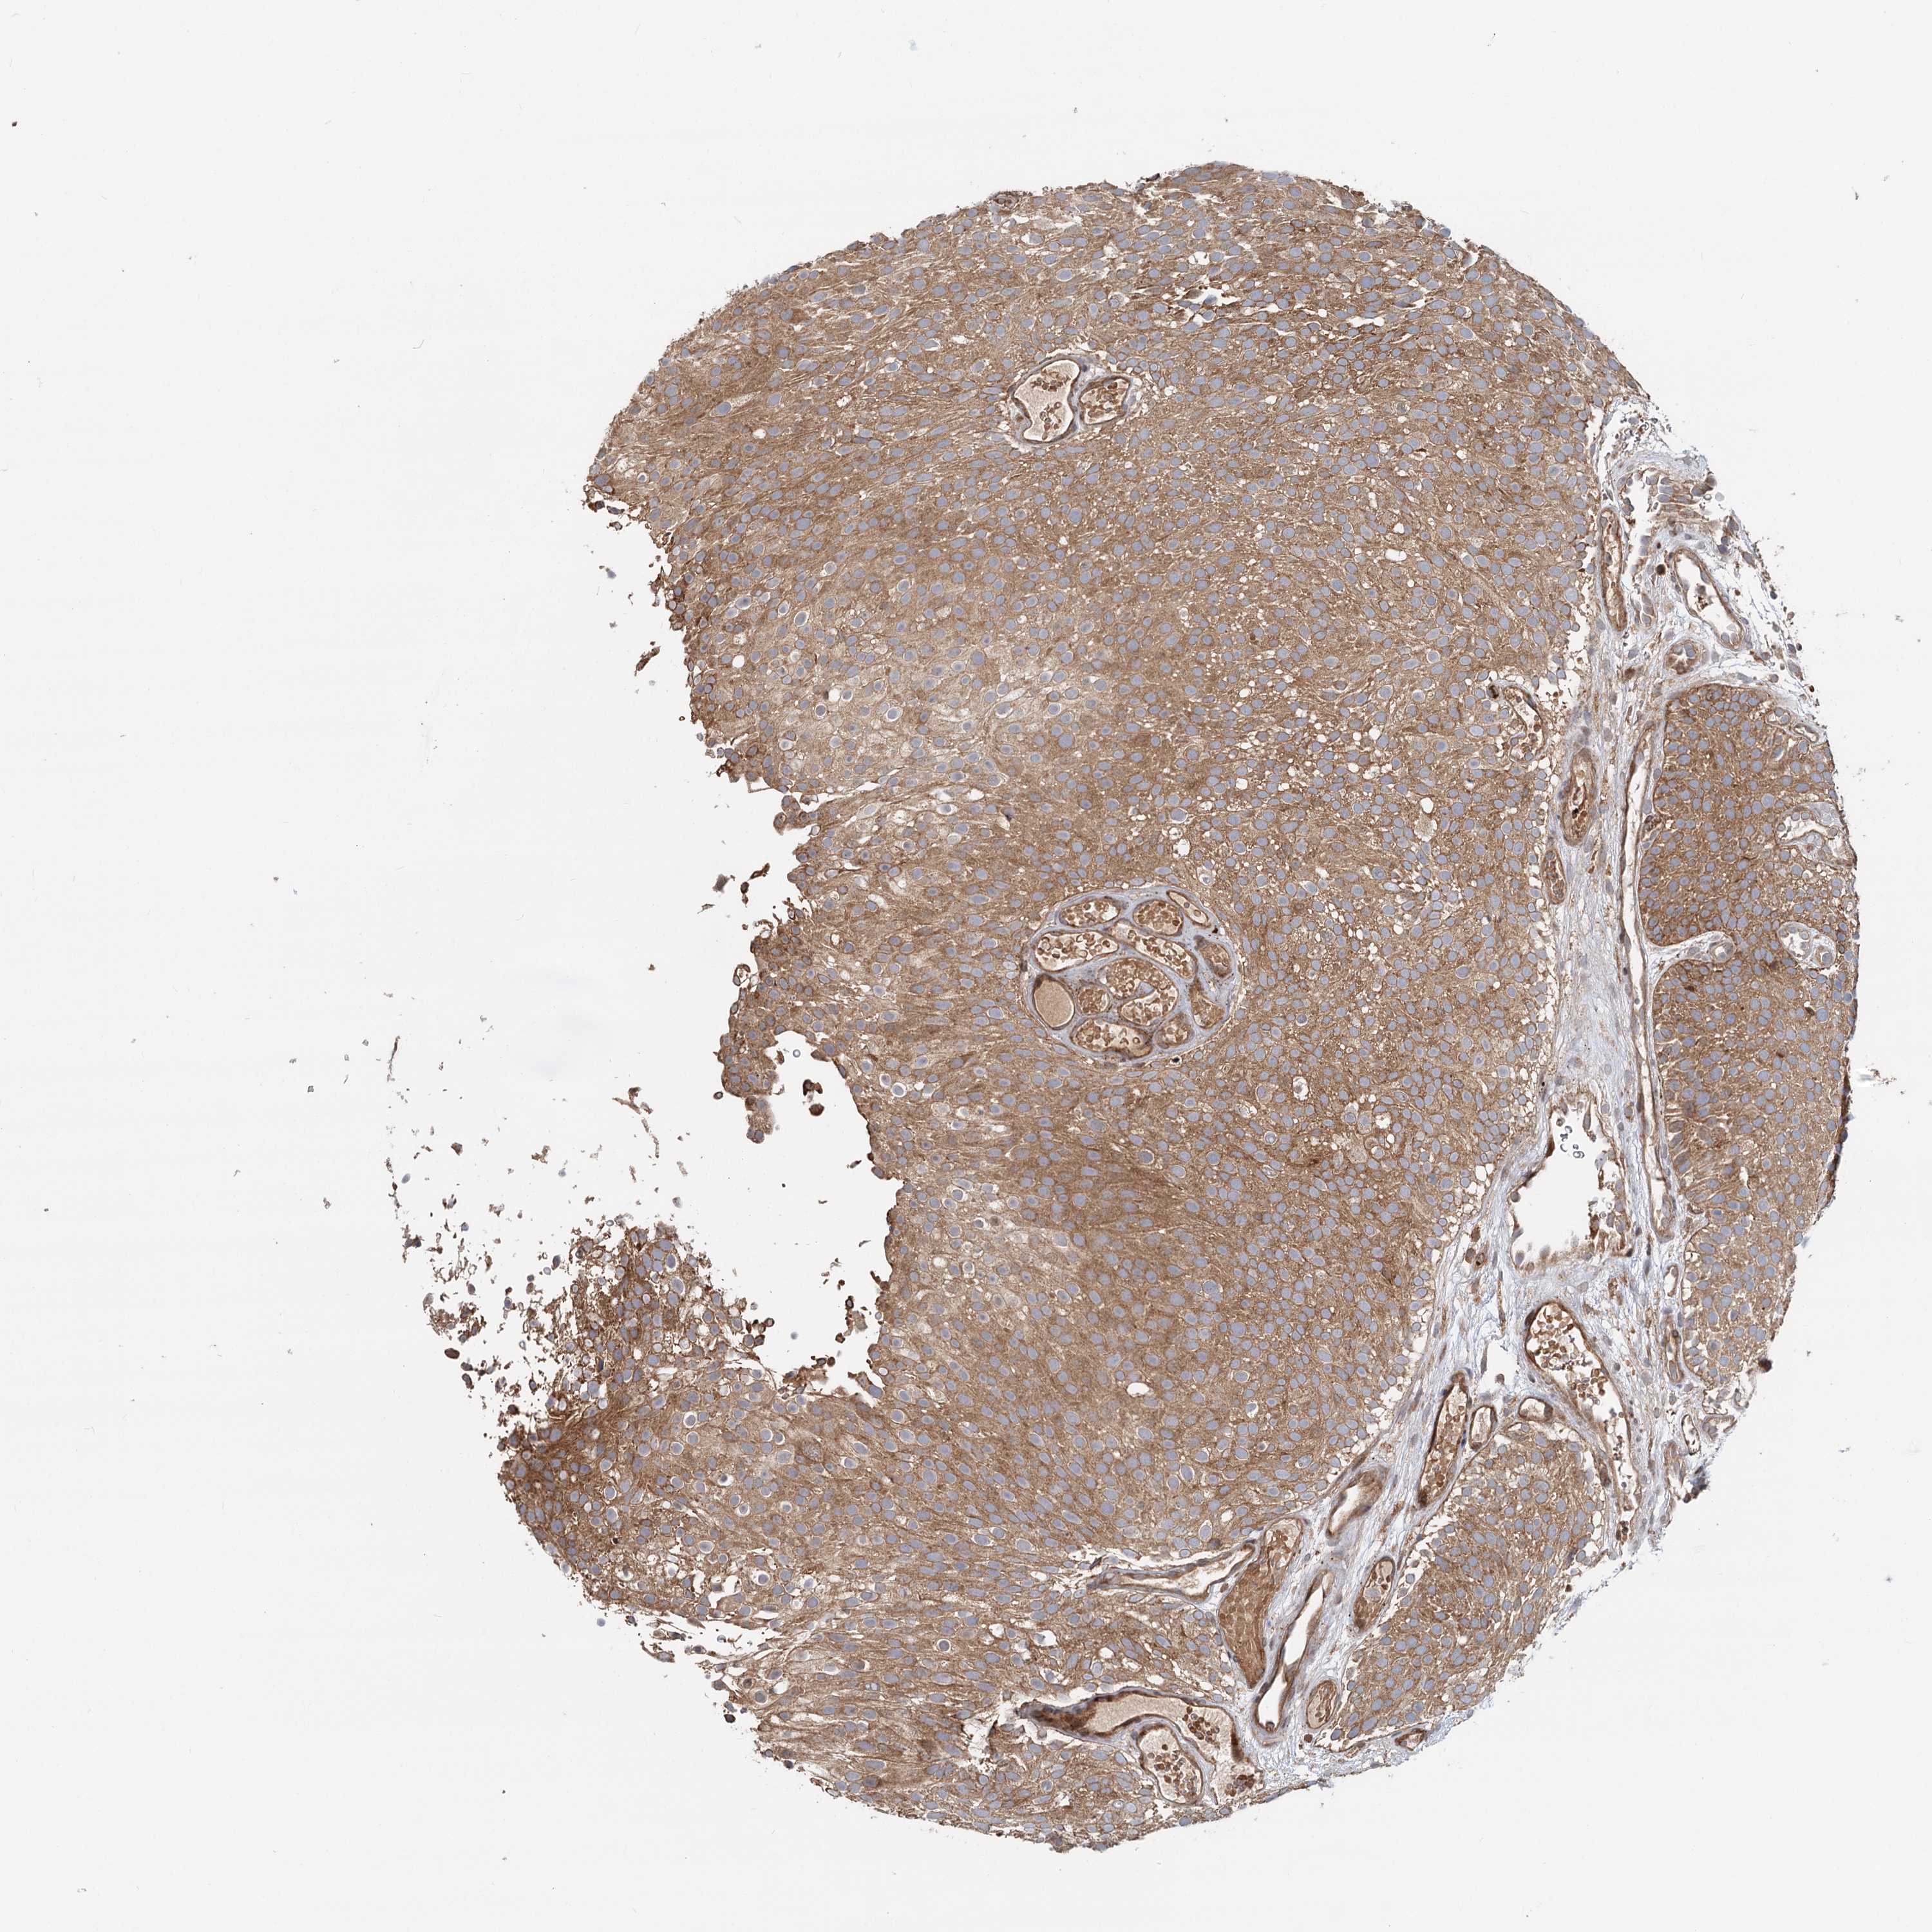

UROTHELIAL CANCER - Protein expressioni

A mouse-over function shows sample information and annotation data. Click on an image to view it in a full screen mode. Samples can be filtered based on level of antibody staining by selecting one or several of the following categories: high, medium, low and not detected. The assay and annotation is described here.

Note that samples used for immunohistochemistry by the Human Protein Atlas do not correspond to samples in the TCGA dataset.

Antibody stainingi

Antibody staining in the annotated cell types in the current human tissue is reported as not detected, low, medium, or high, based on conventional immunohistochemistry profiling in selected tissues. This score is based on the combination of the staining intensity and fraction of stained cells.

Each image is clickable and will lead to virtual microscopy that enables deeper exploration of all samples and also displays staining intensity scores, fraction scores and subcellular localization as well as patient and tissue information for each sample.

Antibody HPA038576

Antibody HPA038577

Staining

High

Medium

Low

Not detected

Intensity

Strong

Moderate

Weak

Negative

Quantity

>75%

75%-25%

<25%

None

Location

Nuclear

Cytoplasmic/membranous

Cytoplasmic/membranous,nuclear

Urothelial carcinoma, High grade

Urothelial carcinoma, Low grade

Urothelial carcinoma, NOS